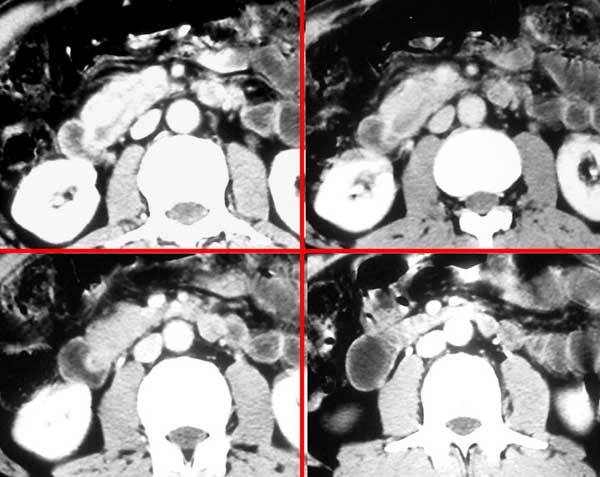

患者,男,57岁,梗阻性黄疸10余天。

这个病例胰头无明显增大,胆总管扩张明显而肝内胆管扩张更不明显,病程较短,

注意到十二指肠乳头明显突出,但尚光滑。分析以下可能性:

1、十二指肠乳头本身的病变,如乳头炎症;

2、急性乳头水肿,胆总管下端结石排石后乳头水肿;

3、壶腹部胆总管下端肿瘤累及十二指肠乳头。

十二指肠乳头粘膜慢性非特异性炎症